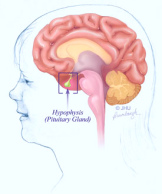

[Studien an Verseuchung

von Knochenmark, Nieren, Leber, Bauchmuskulatur und

Hypophyse (Hirnanhangdrüse) mit Quecksilber]

Korrelation ergab sich wiederum in einer schwedischen

Studie (Weiner / Nylander 1993) auch im Hinblick auf den

Quecksilbergehalt in der Bauchmuskulatur und in der

Hypophyse.

Hypophyse

[22]: Quecksilber aus Amalgam wird ins Blut

übertragen und reichert sich in der Hypophyse

(Hirnanhangdrüse) an, ganz legal, ohne dass

bis heute (2008) ein Richter eingreifen

würde...